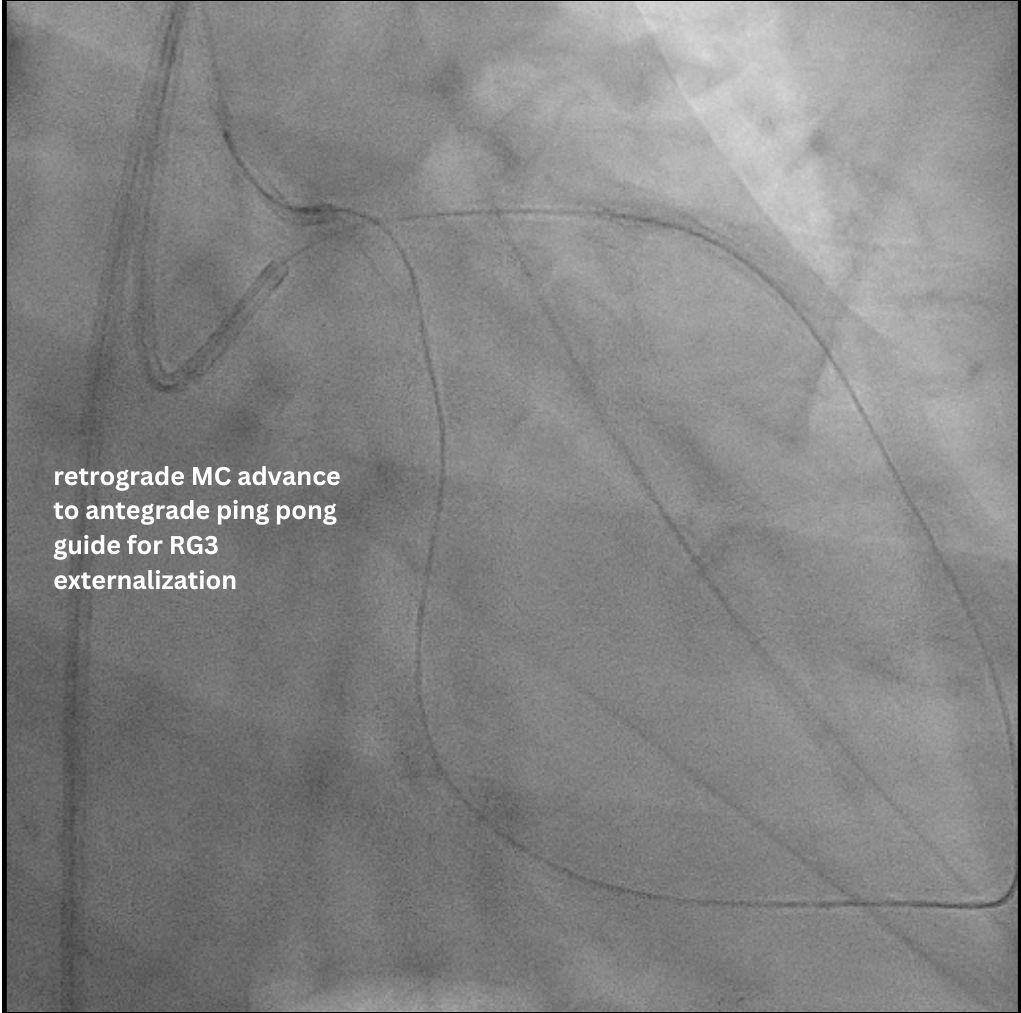

Access was achieved via RRA and US-guided RFA puncture. A 7F SBP 3.5 guide was engaged to LM, and a 6F IL 3.5 guide was in oRCA, confirming no contralateral supply to LCx CTO. After a failed antegrade IVUS guided puncture by GW Gaia Next 2, the strategy shifted retrograde. GW Sion supported by microcatheter Caravel successfully navigated D1 across LAD stent struts, visualizing the ipsilateral epicardial collateral to OM2. The wire was exchanged to SUOH 03 and then advanced to OM2. After initial retrograde wiring failures by a UB3, a Gladius MG successfully crossed the CTO body to pLCx. IVUS to pLCx confirmed retrograde wire in subintimal plane. Multiple attempts R-CART failed in p-mLCx despite wire escalation to GW Gaia Next 3. Repeat IVUS showed enlarging pLCx hematoma, necessitating deployment of a DES (ULTIMASTER NAGOMI 3.0 mm/18 mm) to seal the entry point. Successful stent based R-CART was then achieved with Gaia Next 3, confirmed by IVUS. The IL 3.5 guide was moved to LM as an antegrade Ping-Pong guide for RG3 externalization after successfully advancing retrograde wire and microcatheter to the IL guide. The m-dLCx was prepared by SC balloons and a DES (ULTIMASTER NAGOMI 2.5 mm/50 mm) was deployed to the p-dLCx-OM2, overlapping the proximal DES. A D1 perforation was noted and then successfully treated with fat embolism via the retrograde microcatheter. Final angiogram and IVUS confirmed optimal results.